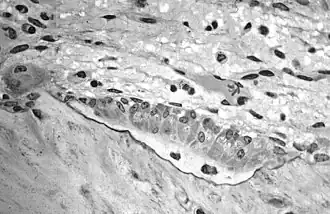

In histology, osteoid is the unmineralized, organic portion of the bone matrix that forms prior to the maturation of bone tissue.[1] Osteoblasts begin the process of forming bone tissue by secreting the osteoid as several specific proteins. The osteoid and its adjacent bone cells have developed into new bone tissue when it becomes mineralized.

Osteoid makes up about fifty percent of bone volume and forty percent of bone weight. It is composed of fibers and ground substance. The predominant type of fiber is type I collagen and comprises ninety percent of the osteoid. The ground substance is mostly made up of chondroitin sulfate and osteocalcin.